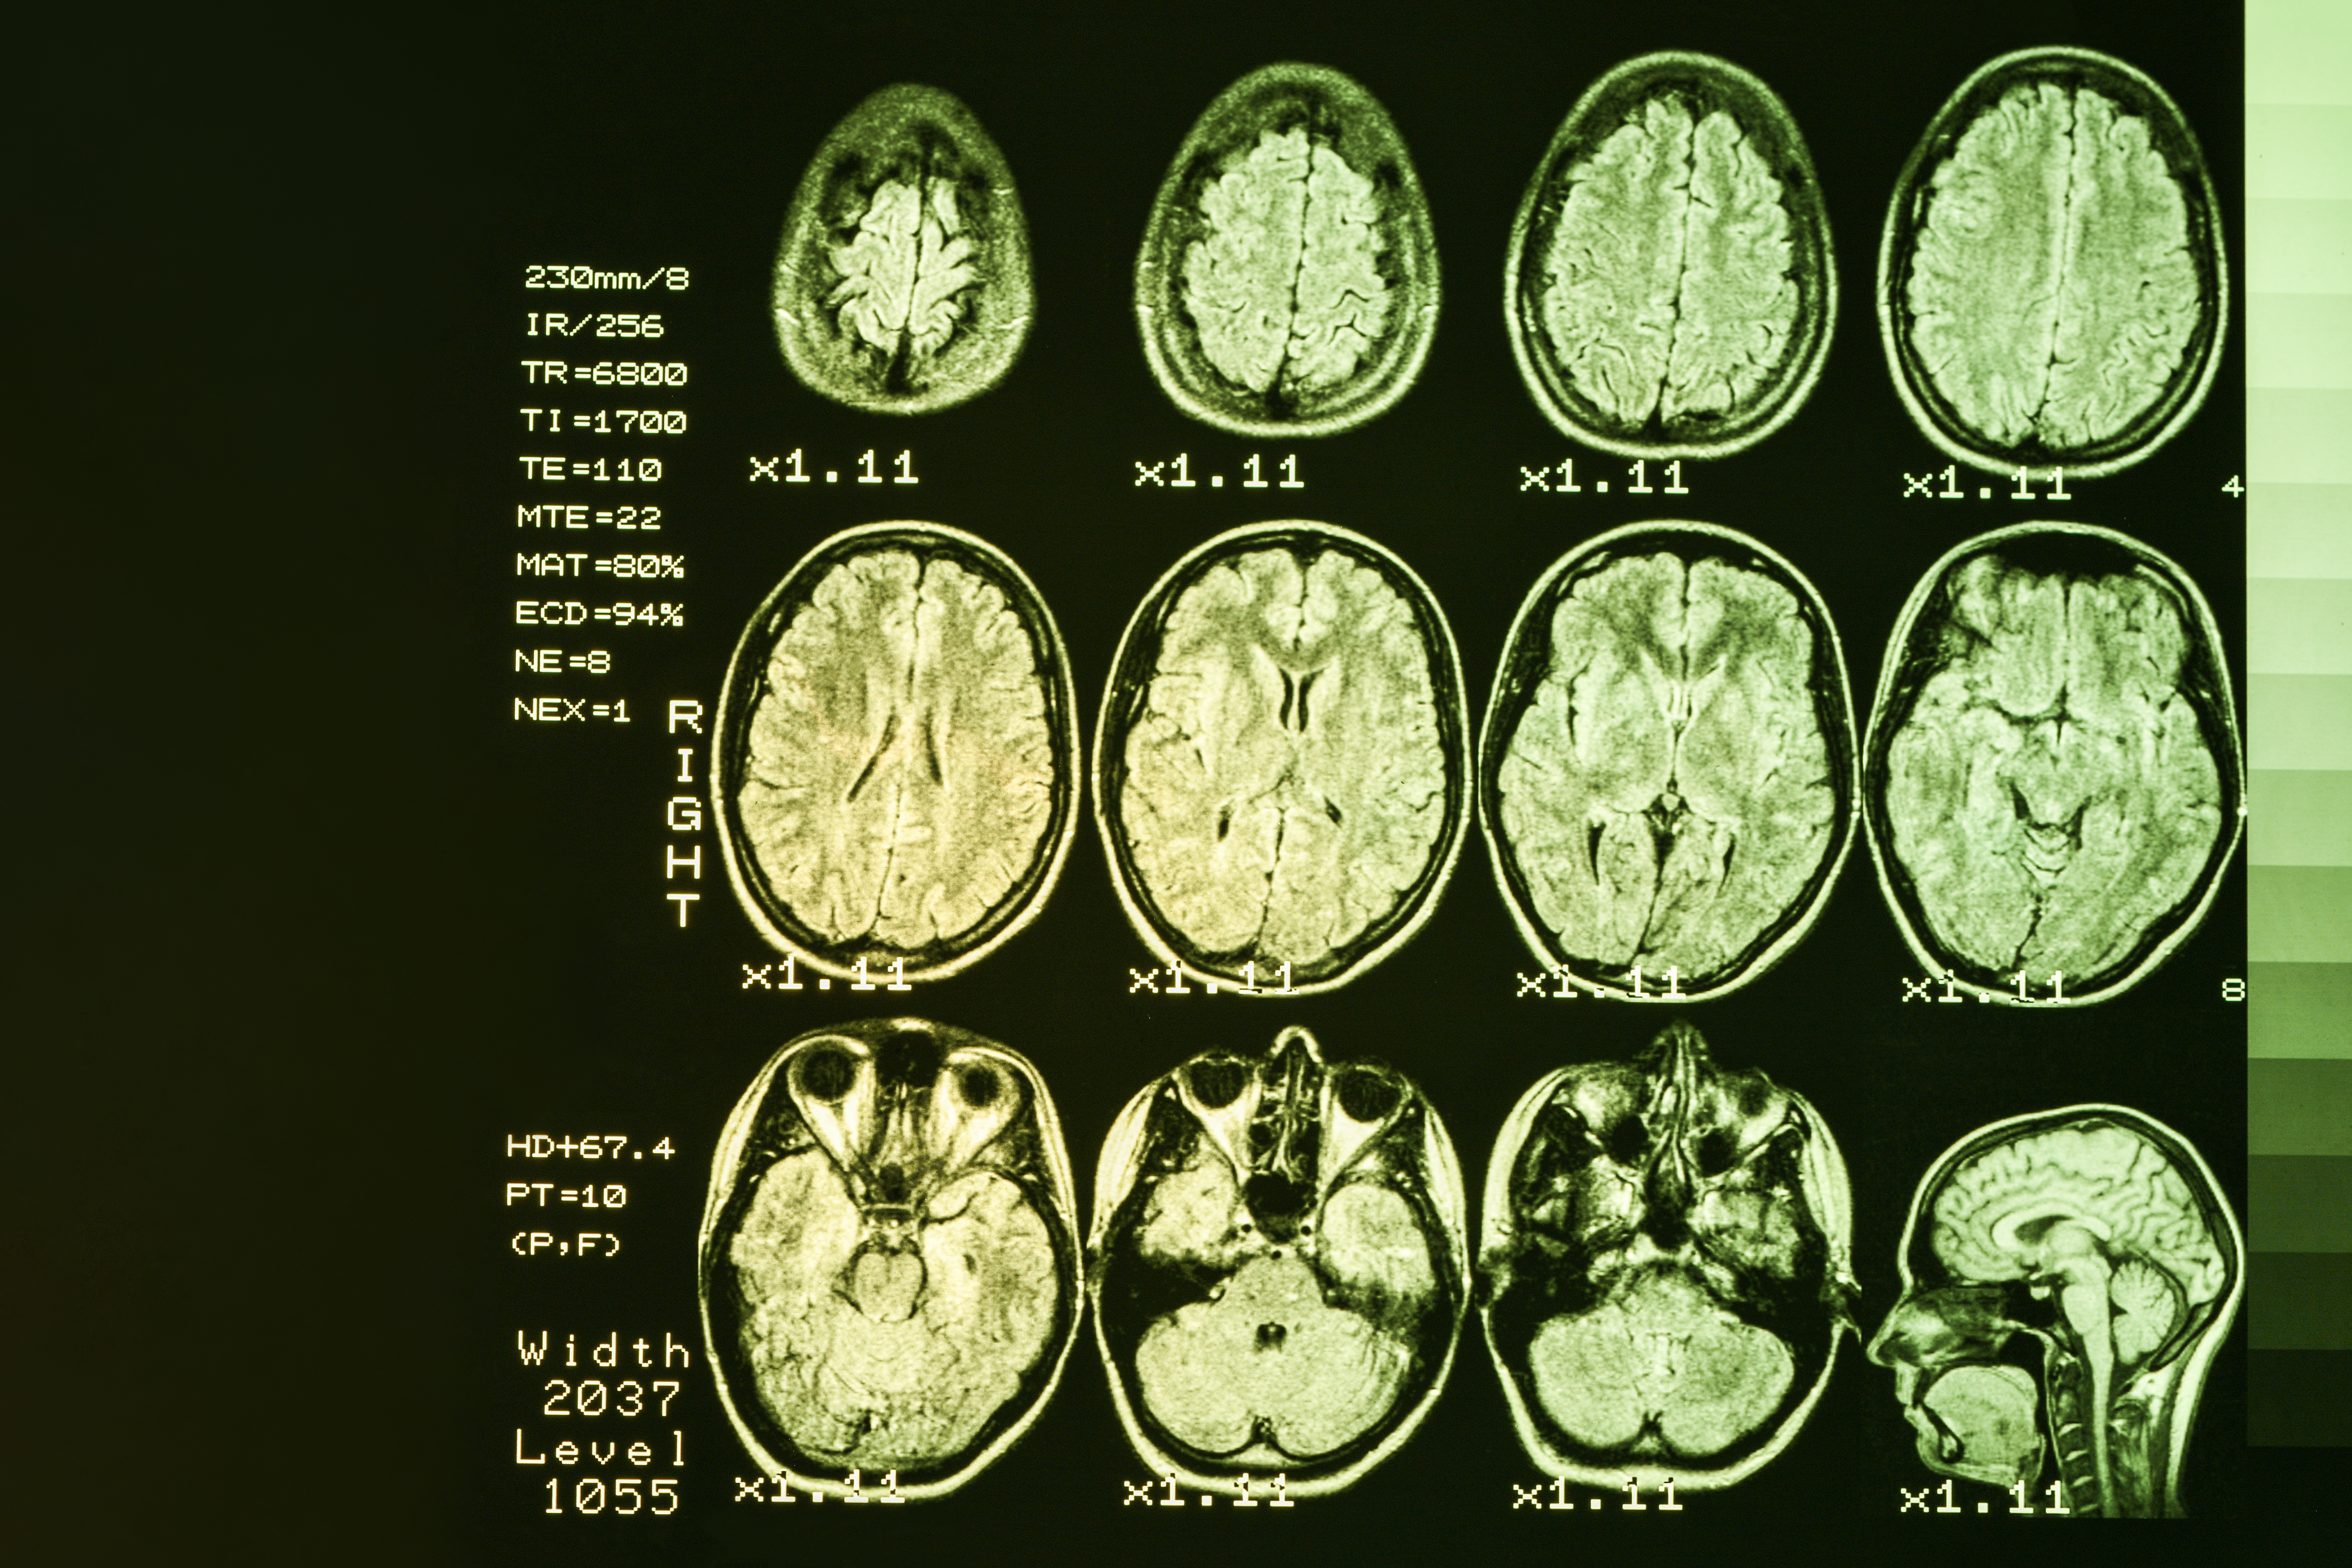

On The Trail Of New Huntington S Disease Treatment Options from www.brainandlife.org Learn more about huntington's disease. Hd manifests by affecting nerves spread throughout just about the entire brain, including the striatum, subthalamic nucleus and substancia nigra. Über 7 millionen englischsprachige bücher. Huntington disease (hd) is an inherited condition that causes progressive degeneration of neurons in the brain. The death of brain cells in certain areas of the brain results in a gradual loss of cognitive (thinking), physical and emotional function. Hd is characterized by progressive physical, cognitive, and psychological deterioration. Hd symptoms include uncontrolled movements, problems with thinking and emotional disturbances. As the disease progresses, the person will become more dependent on caregivers.

Certain areas of the brain are more vulnerable to the effects of nerve damage than others.